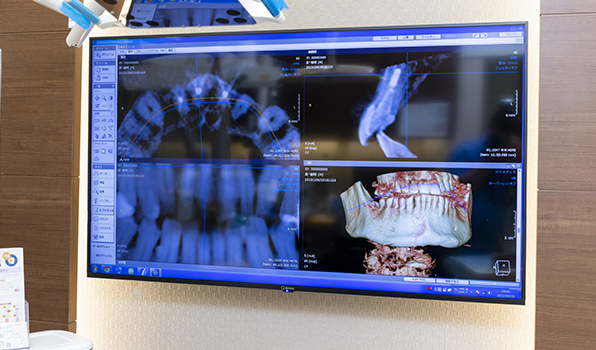

歯科用CT完備

通常、歯の状態を確認する場合、平面のレントゲン写真を使用しますが、平面のレントゲン写真では立体の歯に対して神経の管がどこにあって何本通っているかしっかりと判断することはできません。そこで、三次元的に立体画像で確認することができる歯科用CTを使用し、神経の位置や根管をしっかりと確認します。

精密な治療を皆さまへ提供するためにも、精度の高い診査・診断が重要です。

根管治療にCTはなぜ必要なのですか?

CTを使うことで「見えなかったものが見える」からです。

従来はデンタル写真やパノラマ写真で診断していましたが、これらでは根の先の病巣が映らないことも多く、

しかしCTを用いると、通常のレントゲンでは映らなかった根尖病巣がはっきり見えることが数多くあります。

つまり、「レントゲンでは異常なし」とされた歯でも、CTでは感染が確認されることが少なくありません。

さらにCTは、

• 根管の数や形の確認

• 複雑な根の走行の把握

にも非常に有効です。これにより、治療の精度と成功率が大きく高まります。

言い換えるなら、CTなしで根管治療を行うのは、羅針盤を持たずに大海原へ漕ぎ出すようなものです。

ただし、保険診療ではCT撮影に制限があり、特に前歯や小臼歯では自由に撮影できないのが現実です。当院では必要に応じて自費でのCT撮影を行い、確実に病気を見つけ、正確な治療を行う体制を整えています。